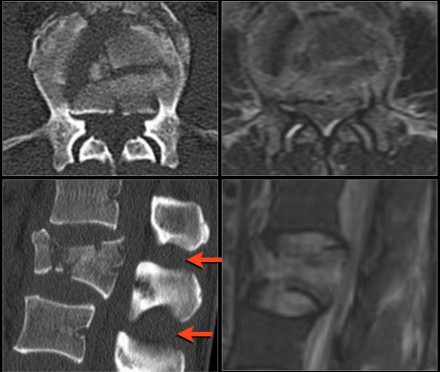

The findings are:

- Morphology: Burst - 2 points

- PLC: very subtle widening of right facet joint - 2 or 3 points

- TLICS based on imaging: 4 or 5 points

A spondylodesis was performed.